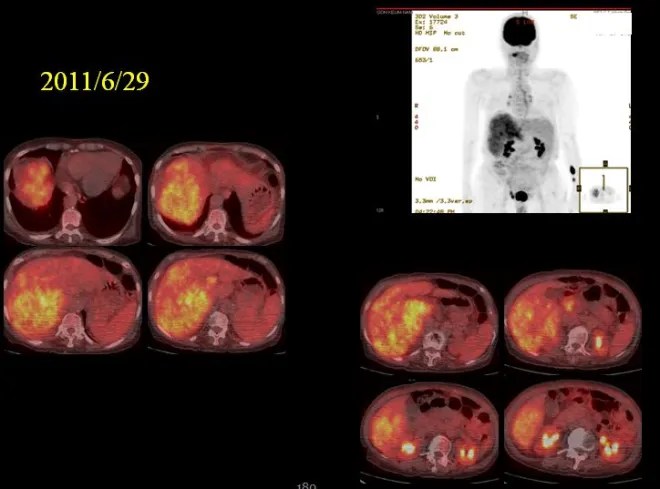

1) 2011년 6월 초진시

PET에서 보이듯이 우측 간엽은 모두가 암이었다. 그래서 보호자들에게 내 생각을 이야기하였다.”나이가 젊으면 한 번 시도해 보겠고 연장이 되시겠지만 현재 흉복수가 모두 차서 알부민도 맞아야 하고 병원에서 심하면 복수를 빼가면서 영양제 공급과 함께 병원을 들락날락 해야 되니 요새같이 바쁜 세상에 가족들도 힘들고, 노인도 오히려 빨리 돌아가시는 게 도와주는 길이라고 이야기 하였다.

그래서 온열찜질을 하는 TDP 기계를 하나 집에서 사 놓고 아침 저녁하시면서 치료를 하시면서 한약을 들게 하였다. 양약은 어차피 태음인에 맞는 넥사바를 쓸 수가 없었기에 한약 단독으로 치료를 시작하였다. 그런데 이분은 놀랍게도 복수가 빠져서 무사히 3년 넘게 견디셨다.